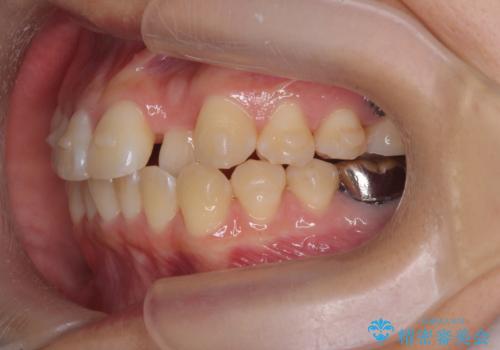

正中のズレ、引っ込んだ前歯の矯正

- 噛んだ時の前歯正中のズレ、引っ込んでいる前歯を治したい。と矯正治療を希望され来院されました。

左上2の前歯はスペースが足りないため、後方に引っ込んでしまっている状態です。

マウスピース矯正システムインビザラインで歯の後方移動、咬合関係の修正を行ったのち、引っ込んでいる左上2をワイヤーを用いて短時間で引き出す治療計画としました。

部分ワイヤー矯正を行なったことで約3ヶ月という短期間で前歯を綺麗に並べることができました。